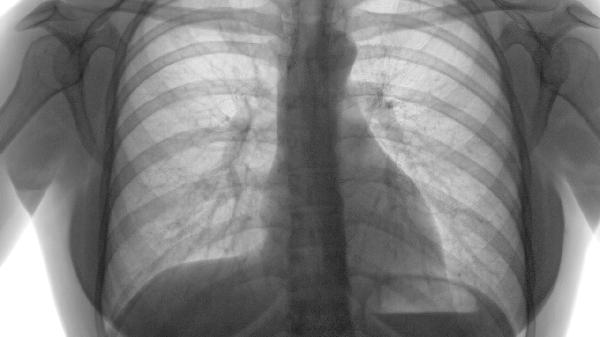

肺气肿的主要症状包括呼吸困难、慢性咳嗽、咳痰、胸闷和活动耐力下降。

早期表现为劳力性呼吸困难,爬楼梯或快步行走时气促明显;随着病情进展,静息状态下也可能出现呼吸费力。这是由于肺泡壁破坏导致气体交换面积减少,同时气道阻力增加所致。患者常描述为“吸气不够用”或“需要用力呼吸”。

胸部压迫感在急性加重期尤为突出,与肺过度充气、膈肌低平有关。患者平卧时症状加重,被迫采取端坐呼吸体位。这种胸闷不同于心绞痛,通常持续数小时且硝酸甘油无法缓解。